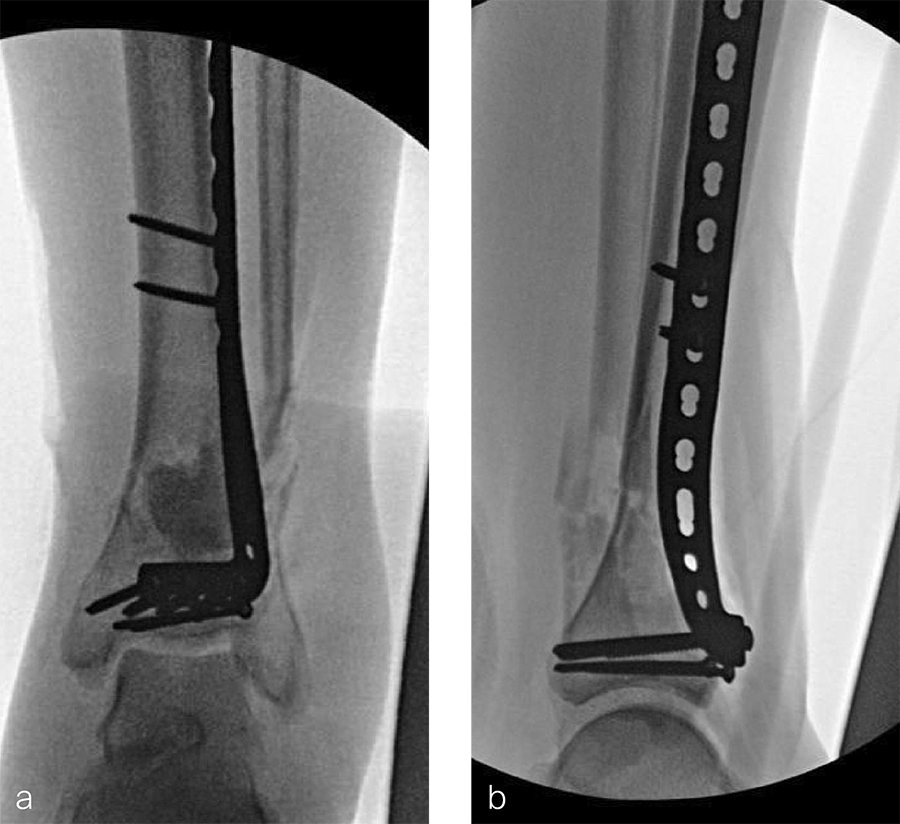

After repeated incision and drainage, 2 days later the fracture was repaired with an anterior lateral tibial plafond plate (Fig 2). Vancomycin and tobramycin impregnated antibiotic beads were placed in the bone defect.

The patient was discharged on hospital day 6 to a rehabilitation facility with his left lower extremity in a splint and touch down weight bear allowance. He returned 2 weeks later with drainage from the medial traumatic wound. In addition, he had a gastrointestinal bleed from use of nonsteroidal antiinflammatory drugs. Once the gastrointestinal bleed was stabilized, he was taken the next day to the OR for another incision and drainage. Further, more significant, devitalized bone was resected, and an antibiotic cement spacer was placed (Fig 3). Deep culture samples were taken despite knowing the antibiotic resorbable beads had been placed in the wound at the time of initial closure. The plate was left in place, but a planned exchange plate/nailing was to be performed pending final culture results.

Two months later, the patient had a staged cement spacer removal and hardware removal followed by a new spacer placement (Fig 4). When microbiological cultures were negative for 5 days he was taken to the OR for definitive fixation and bone grafting. RIA bone graft from the ipsilateral femur was taken, a new anterior lateral plate was placed with an adjunct IM nail (and angle stable screws) as the distal plafond was now one articular block (Fig 5).